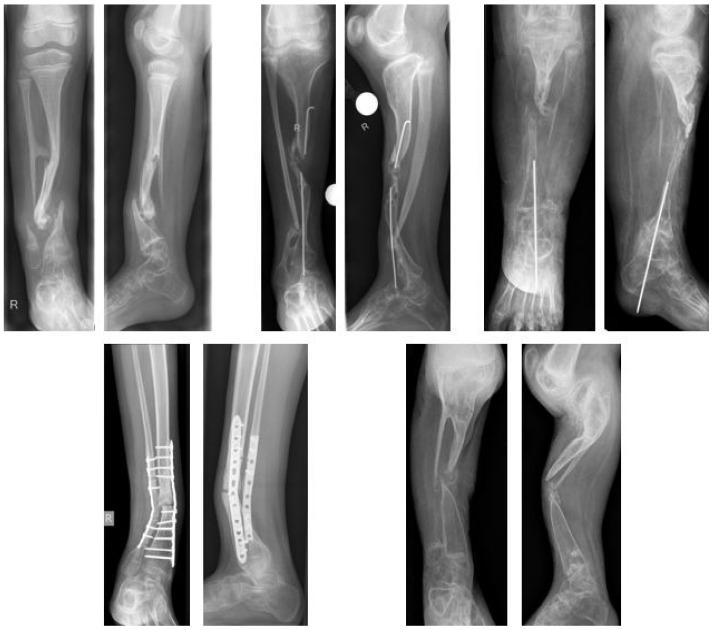

Treatment of congenital pseudarthrosis of the tibia remains a major challenge in pediatric orthopedics. Ideal timing and preference of surgical procedures are discussed controversially. A variety of reconstructive treatment strategies have been described in literature, but so far none has proven its superiority. The aim of treatment is to obtain long-term bone union, to prevent refracture, and to correct angular deformities and leg length discrepancies. This study retrospectively evaluates the outcome of different reconstructive strategies. Sixty-nine patients were identified who presented to our outpatient department between 1997 and 2019. Twenty-six of these patients underwent reconstructive surgical treatment and were included in this study. The study cohort was divided into three groups. Excision of the pseudarthrosis was performed in all patients in Group A and B, and in two patients of Group C. Group A (six/26 patients) received subsequent bone transport through external fixation maintaining original length. In Group B (15/26 patients), patients underwent either previous, simultaneous, or subsequent extrafocal lengthening through external fixation to reconstitute length. In Group C (five/26 patients), internal fixation with intramedullary nails was applied. Radiological and clinical evaluation was performed to assess bone union and complication rates. Results varied considerably between the study groups. Overall, the primary bone fusion rate was 69.2%. There were four refractures, all occurring in Group B. The long-term bone union rate without refracture was 53.8%. The overall complication rate was 53.8% and 23.1% showed persistent pseudarthrosis. Two secondary amputations were performed due to failed bone fusion. In conclusion, excision of the pseudarthrosis and extrafocal lengthening achieves a satisfying bone union rate and limb reconstruction, while bone transport does not offer significant advantages but shows higher complication rates. Intramedullary stabilization should be applied to maintain bone union, but shows lower bone union rates when used as a stand-alone treatment regimen. Regardless of the primary bone fusion rates, the probability of long-term bone union remains unpredictable.

小儿骨科中,胫骨先天性假关节的治疗仍是一项重大挑战。手术时机的选择和手术方式的偏好一直存在争议。文献中描述了多种重建治疗策略,但到目前为止,尚无一种策略证明其优越性。治疗的目的是实现长期骨愈合,预防骨折再发,并纠正成角畸形和肢体长度差异。本研究回顾性评估了不同重建策略的治疗效果。确定了1997年至2019年间在我院门诊就诊的69例患者。其中26例患者接受了重建手术治疗并纳入本研究。研究队列分为三组。A组和B组的所有患者以及C组的2例患者均进行了假关节切除。A组(6/26例患者)随后通过外固定进行骨搬运,保持原长度。B组(15/26例患者)患者通过外固定进行术前、同期或术后病灶外延长以恢复长度。C组(5/26例患者)采用髓内钉内固定。进行影像学和临床评估以评估骨愈合情况和并发症发生率。各研究组的结果差异很大。总体而言,初次骨融合率为69.2%。发生了4例骨折,均发生在B组。无骨折的长期骨愈合率为53.8%。总体并发症发生率为53.8%,23.1%表现为持续性假关节。因骨融合失败进行了2例二期截肢。总之,假关节切除和病灶外延长可实现令人满意的骨愈合率和肢体重建,而骨搬运没有显著优势,但并发症发生率较高。应采用髓内固定来维持骨愈合,但作为单一治疗方案使用时骨愈合率较低。无论初次骨融合率如何,长期骨愈合的可能性仍然不可预测。